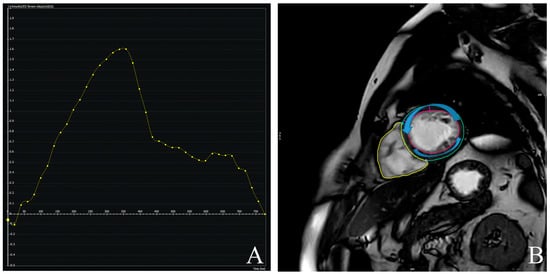

2.2. CMR Assessment

3.2. CMR-Derived Structural and Functional Parameters

3.4. Prognostic Value of CMR-Derived LV-Torsion